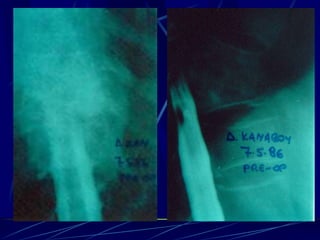

Φυματίωση της σπονδυλικής στήλης